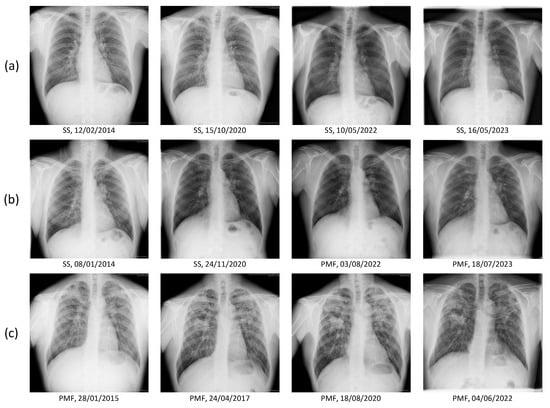

2.2. Image and Clinical Data

3.2. Ablation Study: Justification of Image Segmentation Method